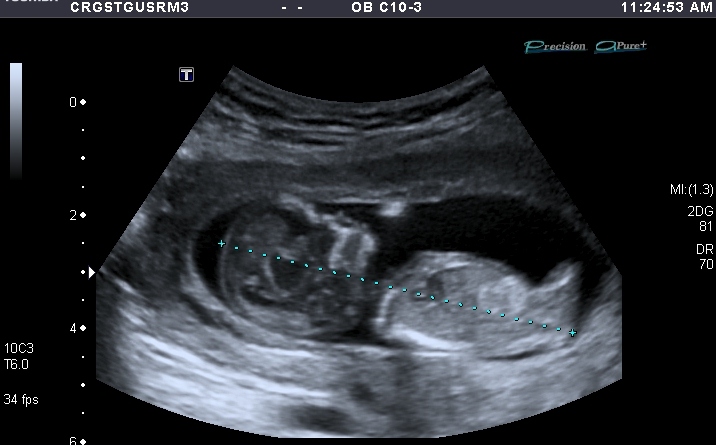

1st and 2nd I thought boy.

I'm going to say boy for the 1st & 2nd picture definetly, but the 3rd picture throws me somewhat!